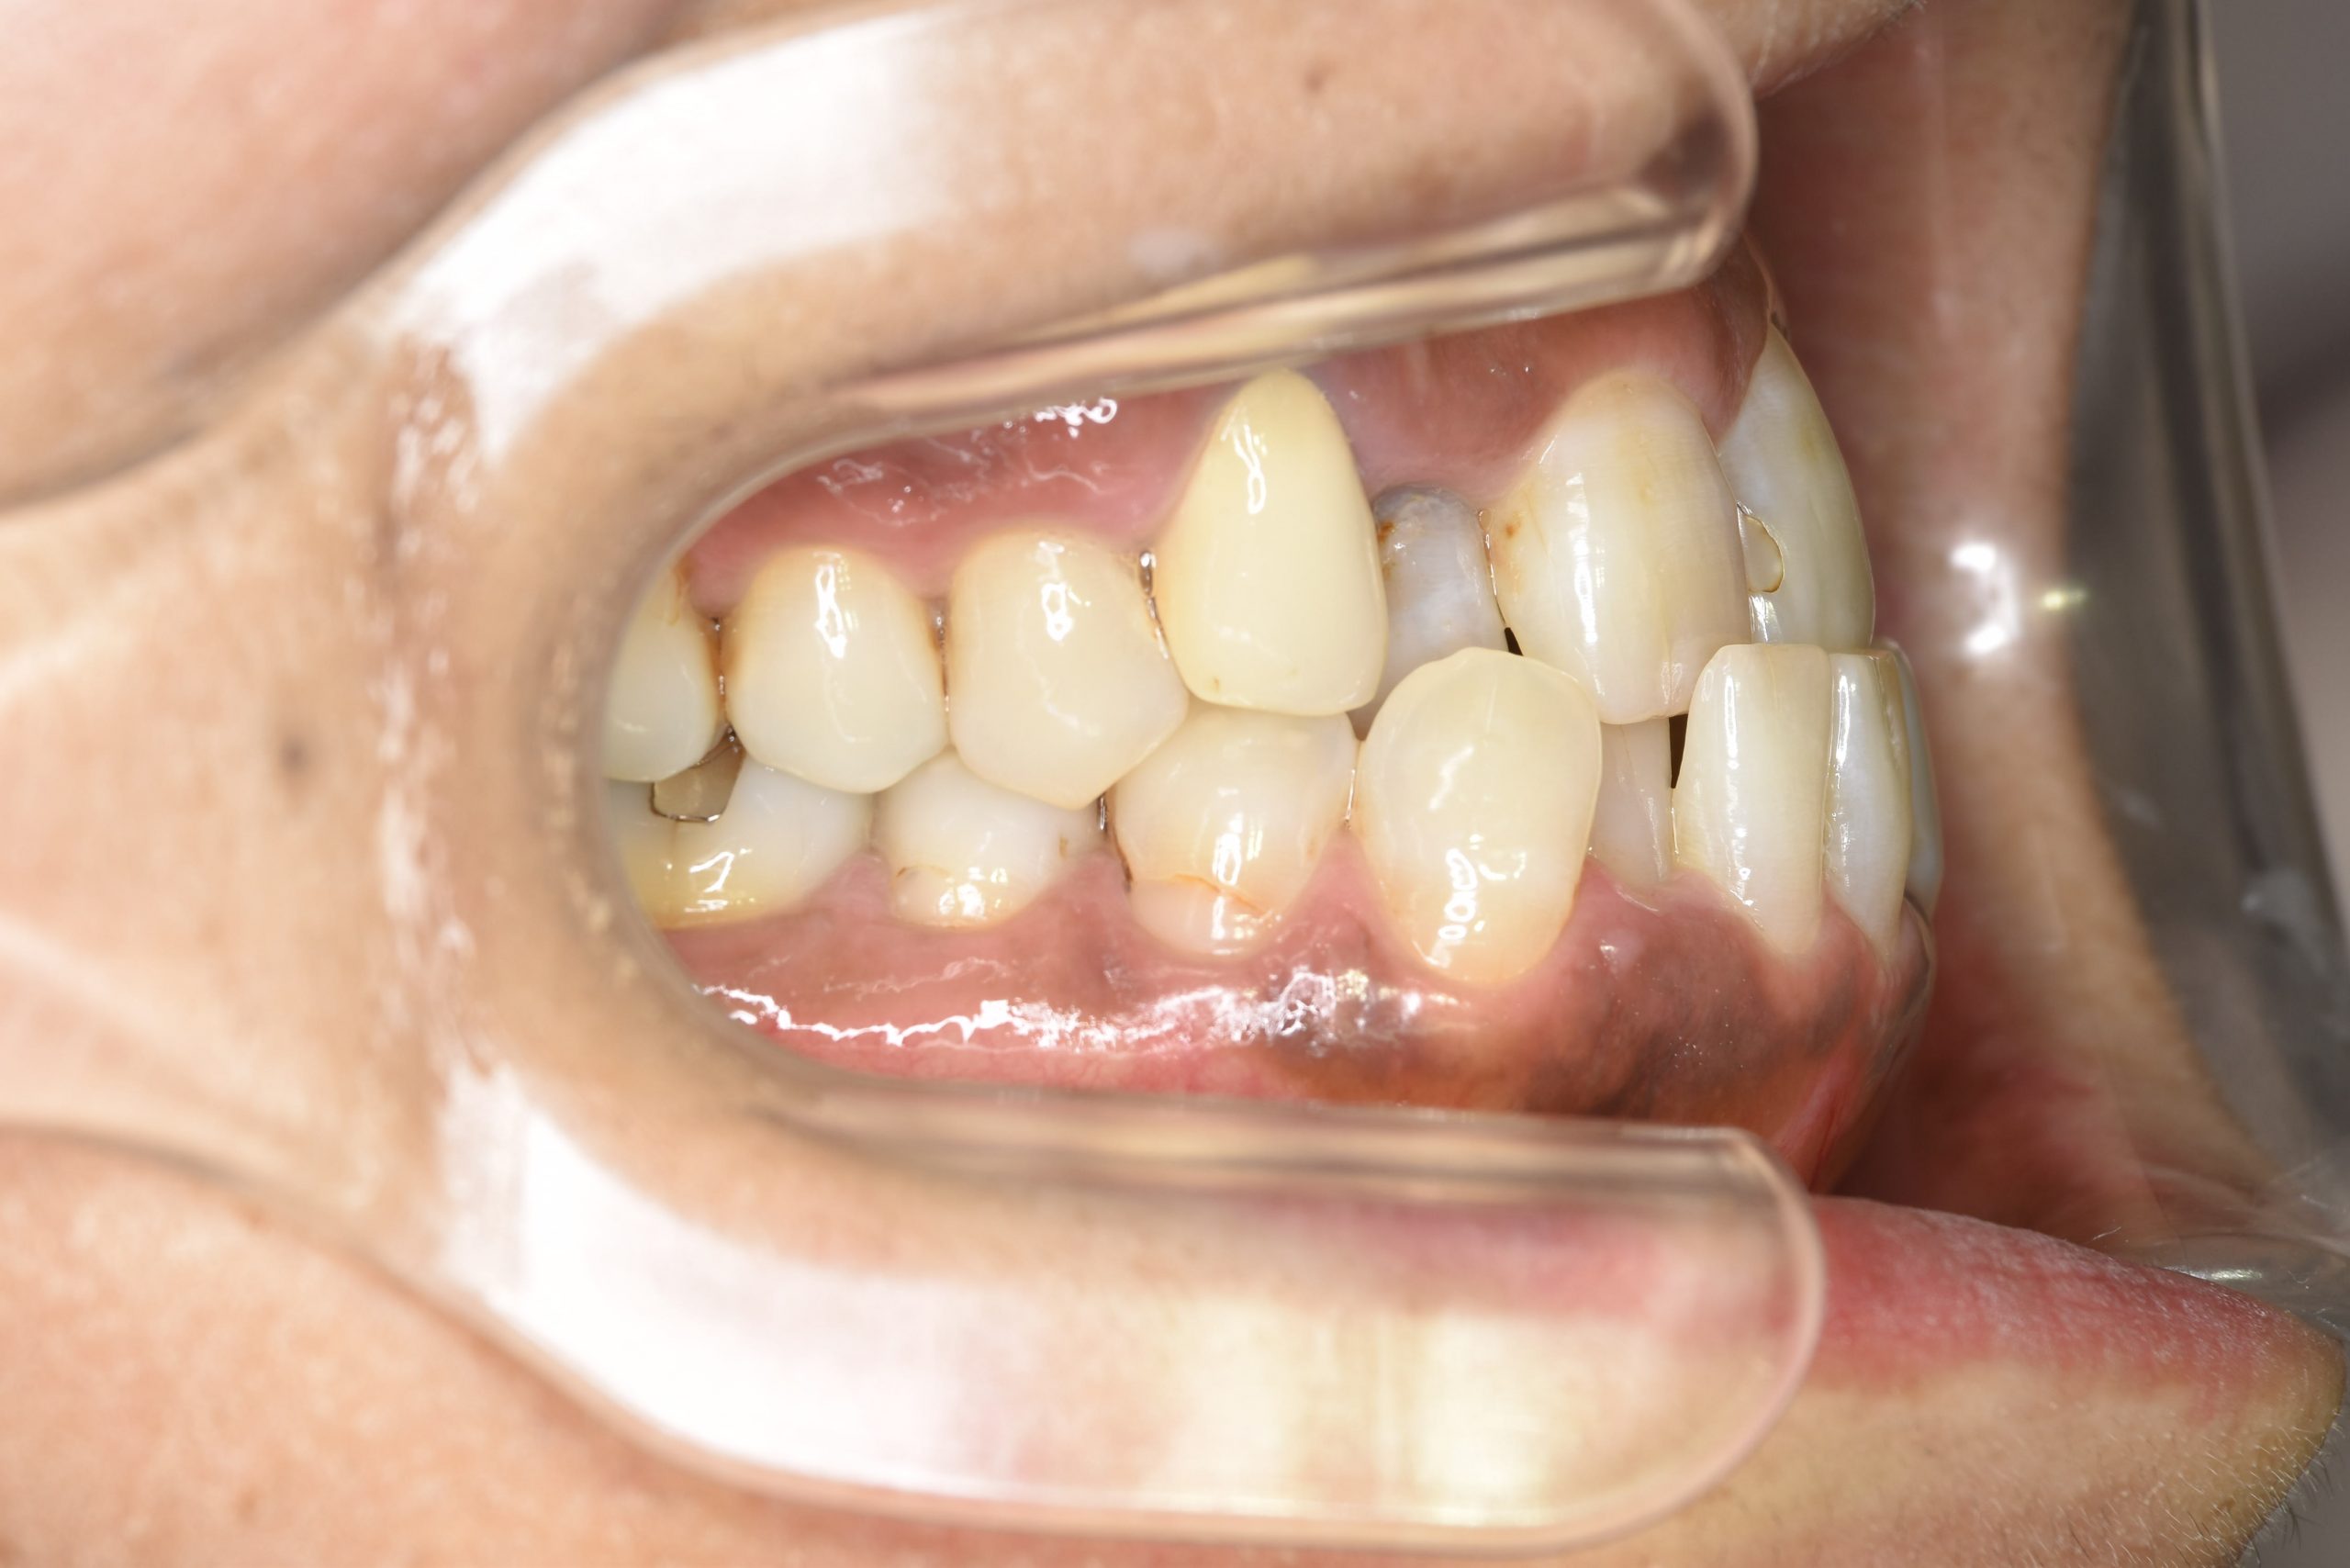

ビフォー

ワイヤー矯正治療|症例_588

主訴 かみ合わせ ※抜歯あり

施術内容 MSEと下顎リンガルアーチを用いて上下顎骨を拡大した。

その後下顎前歯を1本抜歯してマルチブラケット装置を用いて

歯牙を配列し良好な咬合を獲得した。側貌は改善した。